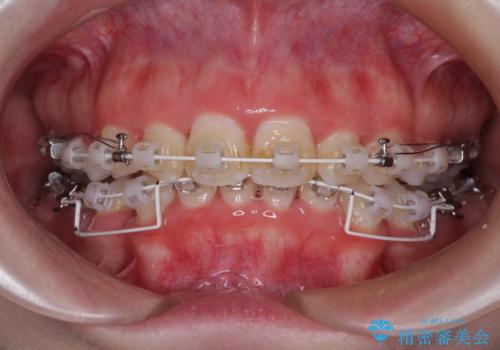

- 矯正装置

- 審美装置

下顎前歯が隠れるほどのディープバイトであり、それによる顎の負担も大きかったため、ディープバイトもしっかりと改善できるよう、表側のワイヤー装置にて矯正治療を行うこととしました。

ディープバイトは、治療を行っていた我々も驚くほど、短期間で劇的に改善することができました。